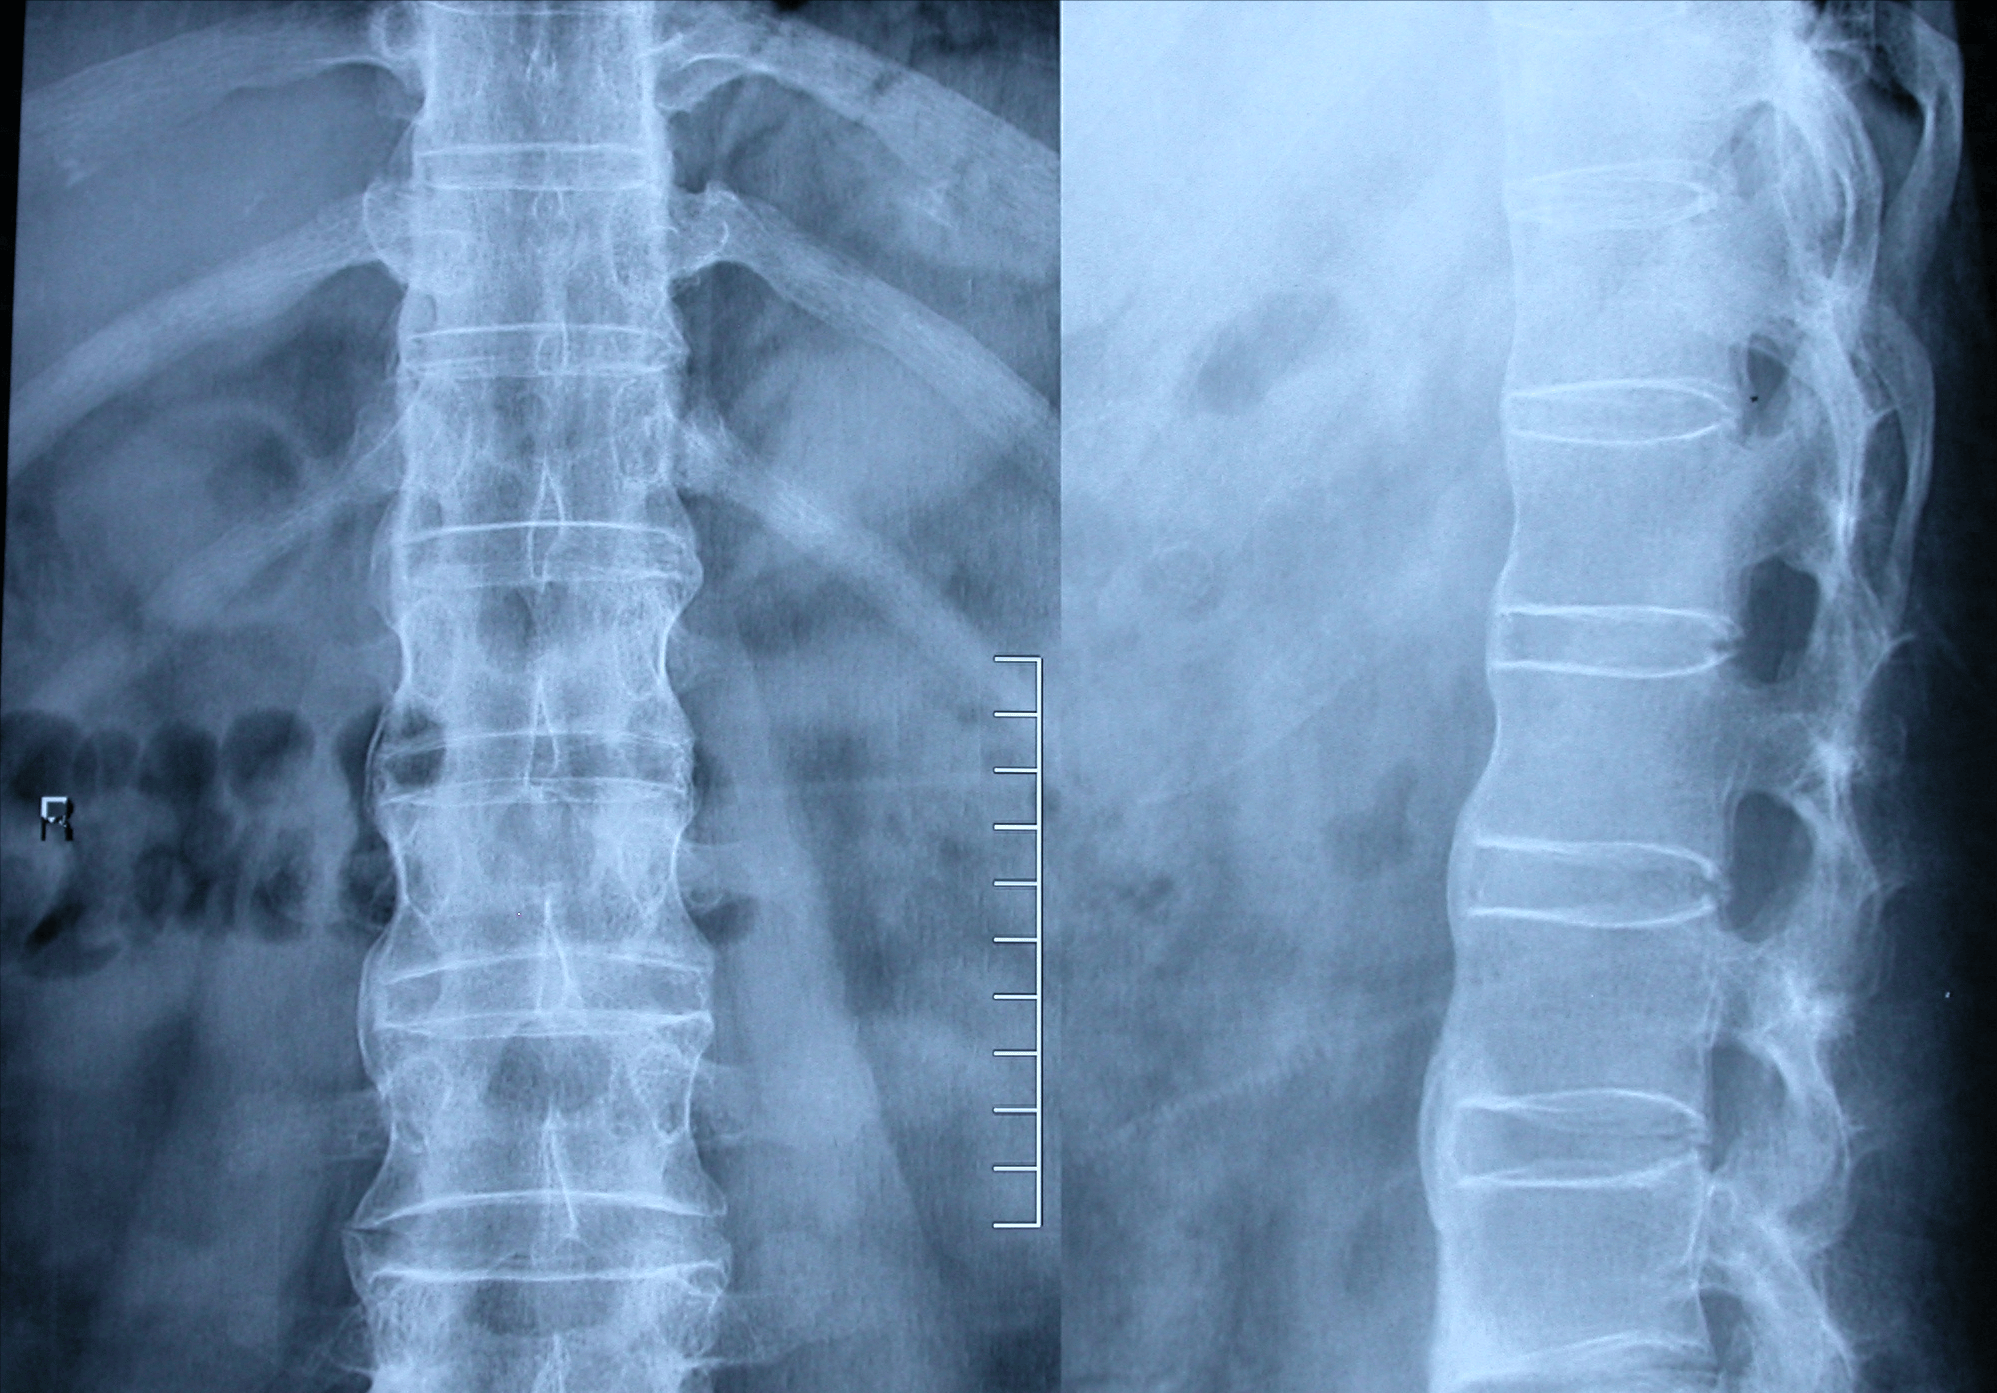

强直性脊柱炎影像

强直性脊柱炎影像全解析:56岁男性患者的ct与mri诊断之旅